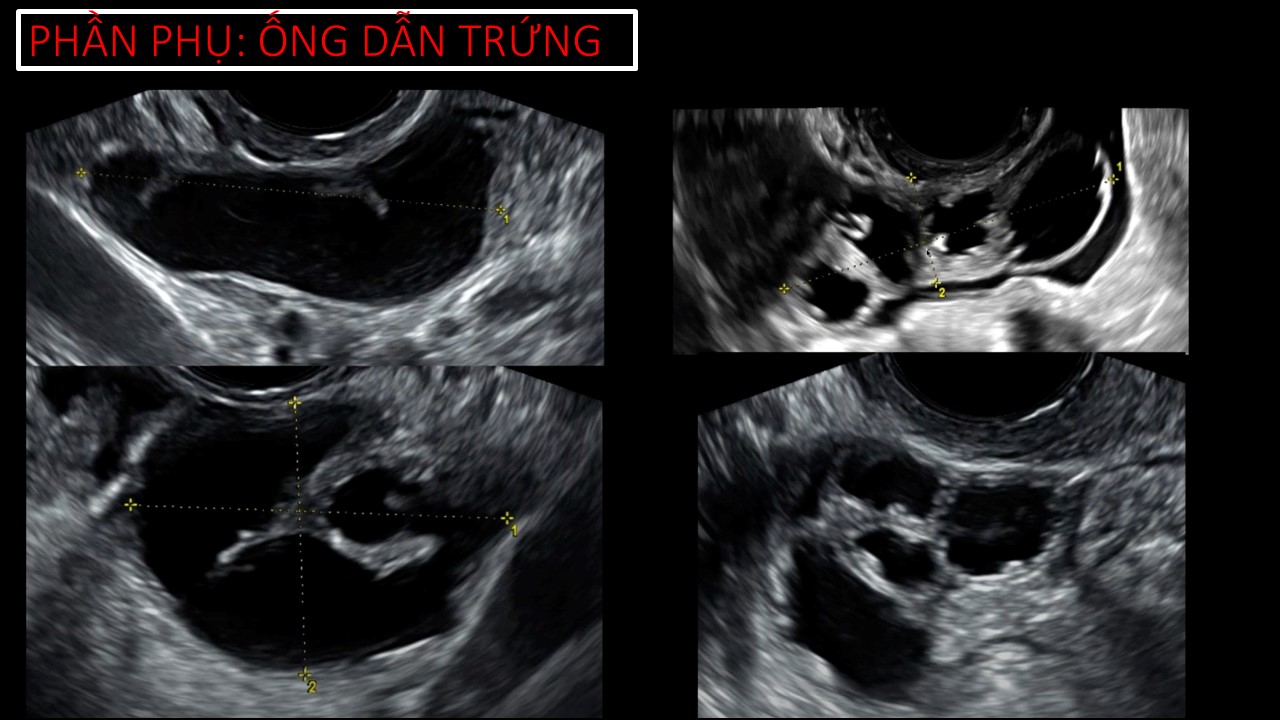

Vai trò của siêu âm trong chẩn đoán và điều trị hiếm muộn